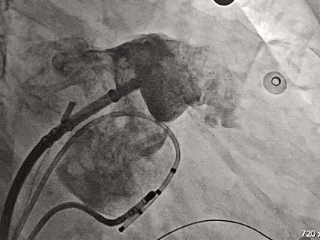

射频消融

术中DSA造影复测缺损

输送内鞘并进行鞘管锁定

封堵器展开